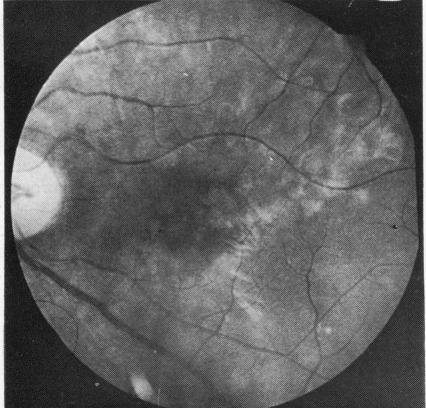

Periarteritis nodosa and thrombotic thrombocytopenic purpura in siblings is reported. In both patients a localised serous retinal detachment and lesions of the retinal pigment epithelium had developed owing to choroidal vascular obstruction. These cases support the suggested possible relationship between the two conditions.

据报道,同胞兄妹患结节性多动脉炎和血栓性血小板减少性紫癜。两名患者均因脉络膜血管阻塞出现局限性浆液性视网膜脱离和视网膜色素上皮病变。这些病例支持了这两种疾病之间可能存在关联的观点。